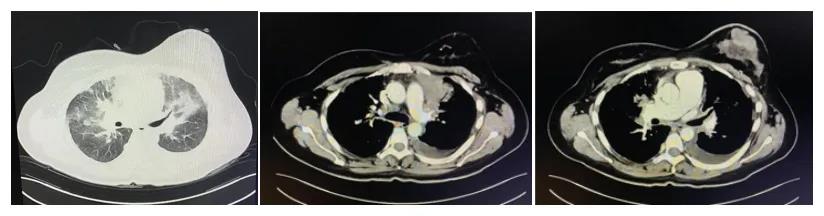

如何治疗乳腺癌,需先完善乳腺肿物穿刺活检,病理明确诊断及免疫组化分型后再定治疗方案,在超声科配合下,患者顺利完成左乳肿物穿刺活检术,病理结果提示患者为HR阳、HER-2阳性乳腺癌,依据最新版CSCO及CACA指南,冀主任制定化疗联合靶向治疗方案,即白蛋白结合紫杉醇联合帕妥珠曲妥珠单抗皮下注射,患者第1周期用药结束后,于床旁活动时出现呼吸困难、喘憋明显,伴血压升高、心率加快,口唇四肢明显紫绀,经吸氧及应用平喘、改善呼吸药物均不见好转,情况危急,请MICU急会诊后立即转入MICU抢救,经高流量吸氧、积极治疗心衰、呼衰、控制心率、胸腔穿刺抽液术放胸水治疗后,患者呼吸困难等不适明显好转,可短时间平躺,完善肺增强CT,发现双肺间质性肺水肿,且左肺上叶、右肺门占位,考虑恶性可能,患者病情逐渐平稳后再次转回肿瘤一科,胸水留病理找到恶性肿瘤细胞,考虑乳腺癌转移来源,冀主任考虑可给予胸腔局部灌注洛铂控制胸水,患者顺利完成第1周期化疗及灌注治疗。

第一次入院肺增强CT